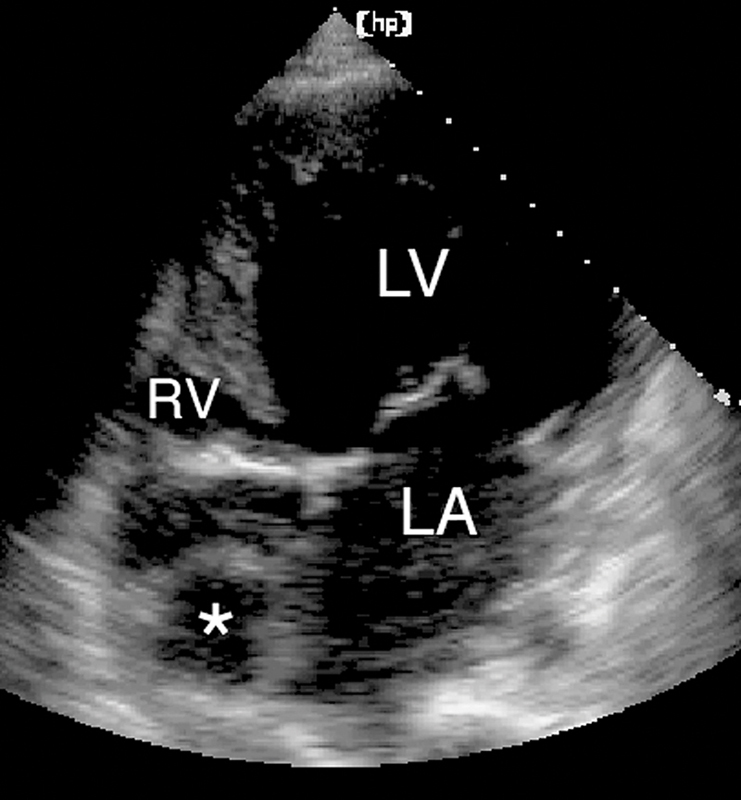

فحوصات تشخيصية لبعض امراض القلب والشرايين التاجية